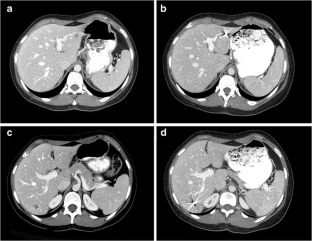

Fig. 1